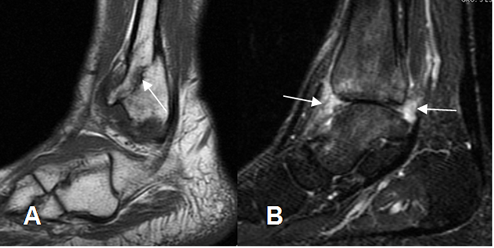

Fig 45. Artropatía neuropática. Patrón atrófico.

A: RM sagital en T1. Fractura oblicua en el maléolo externo, en proceso de consolidación, con persistencia del dolor.

B: RM sagital en STIR. Disminución del espacio tibioastragalino, con edema de ambos huesos y sinovitis asociada.